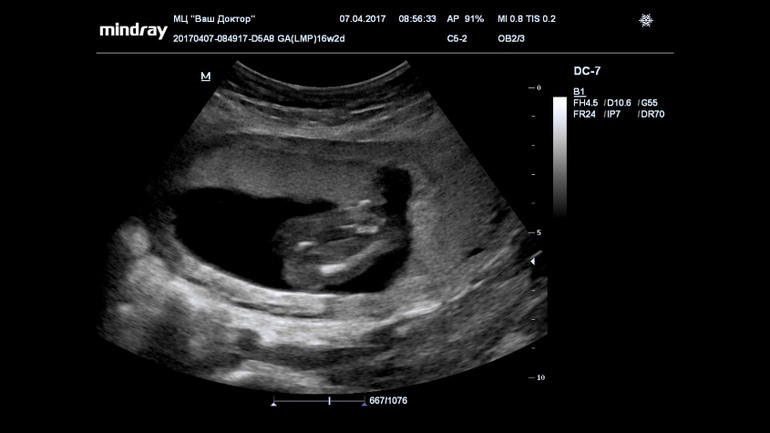

Ну девчуля же? Кто разбирается?

Пол малышаВсе 16 недель была просто уверенна, что в домике живет сыночка, а тут на УЗИ огорошили, что у нас там девица-красавица! Я конечно прибываю в небольшом шоке, но БЕЗУМНО этому рада!!!!!

Записали нам диск, все выходные пересматривала, сделала несколько фото, что скажете?